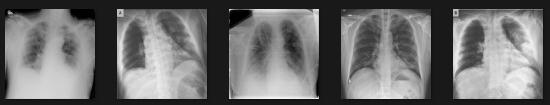

In most cases, the ranges of symptoms of pneumonia andtheCovid 19virusarethesame.Bothareinfectionsof the lungs. Hence, the dataset consists of three separate datasetsofX raysofthechest(COVID 19patients,normal people,andpneumoniapatients).Thereare300photosin all(100COVID 19images,100pneumoniaimagesand100 healthy images). After that, the datasets are divided into two sections: training and testing the classifiers. Fig 1,2,3 showsanexampleofchestX rayimagecollections. Fig.1.

PNEUMONIAchestX Rayimages

Fig.2.